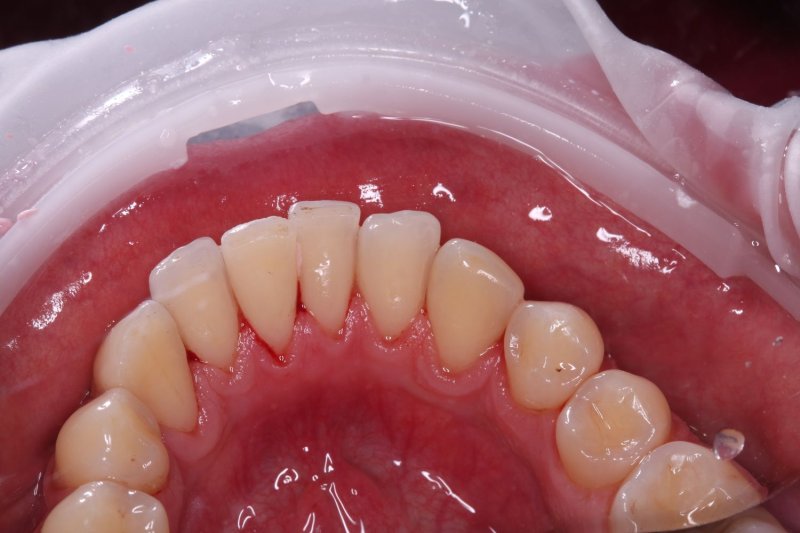

После

udalenie-naleta-ot-kureniya-gbt-posle

Результат

Полное удаление всех видов загрязнений: пигментного налета от кофе и сигарет, мягкого бактериального налета и зубного камня. Зубам возвращена природная белизна и гладкость. Свежесть дыхания и здоровый вид десен восстановлены.